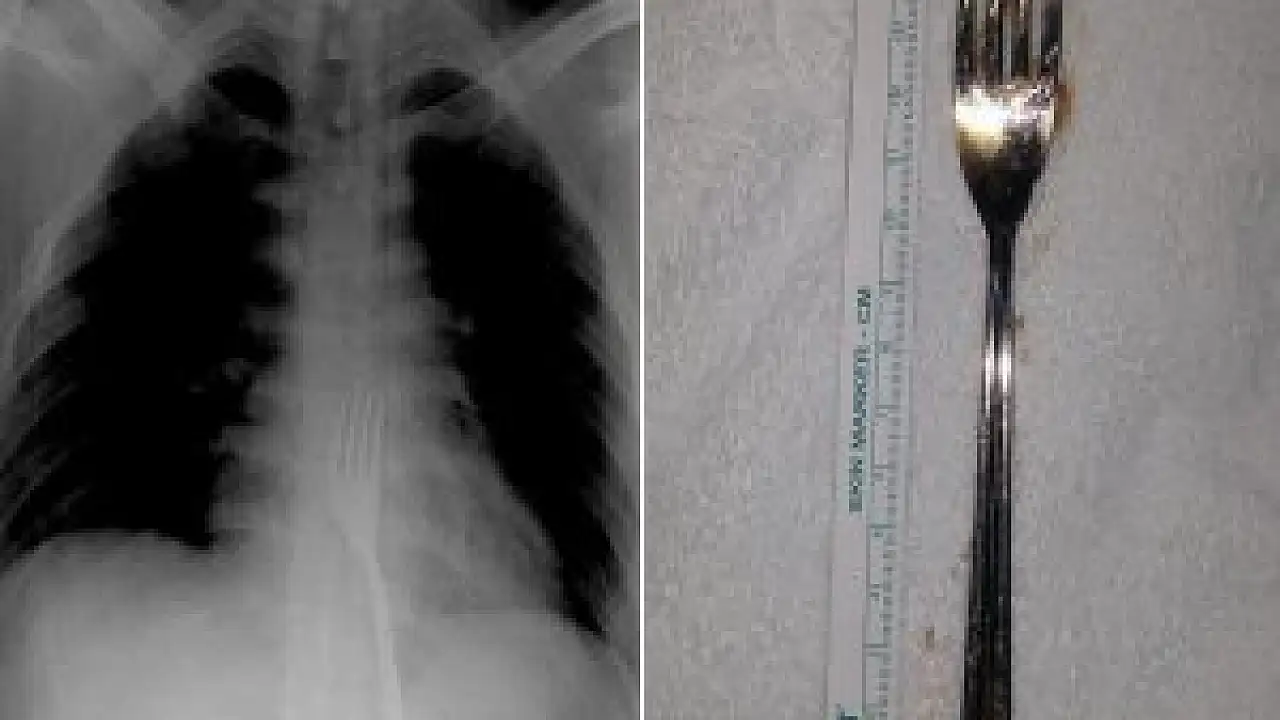

Çekilen röntgen filmlerinde, 15 santimetrelik çatalın midede olduğu görüldü. Metal çatal, O.A'nın midesinden ameliyatla çıkarıldı. O.A, taburcu edildi.

Hastanenin Genel Cerrahi Anabilim Dalı Öğretim Üyesi Prof. Dr. Mehmet Erikoğlu, AA muhabirine yaptığı açıklamada, büyük olması nedeniyle çatalı ameliyatla mideden çıkardıklarını anlattı.

Küçük yabancı cisimlerin mideden atılabildiğini anlatan Erikoğlu, "Yabancı cisim düz yutulmuş olsaydı, ciddi sıkıntılar doğabilirdi. Çatal tersten yutulduğu için vücuda bir zararı olmamış. Bugüne kadar çatal yutmasıyla ilk kez karşılaştık." dedi.